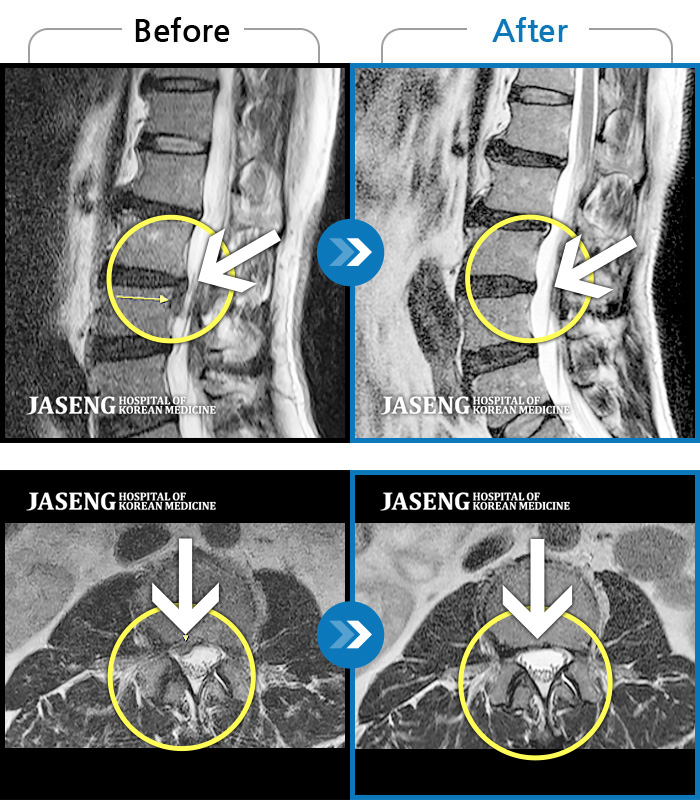

MRI 결과는 추간판협착증 2군데와 추간판탈출되어 터져서 디스크가 좌측으로 흘러내려 좌측 신경을 넓게 누르고 있는 곳이 1군데로 예상보다 심각한 상태였더군요.